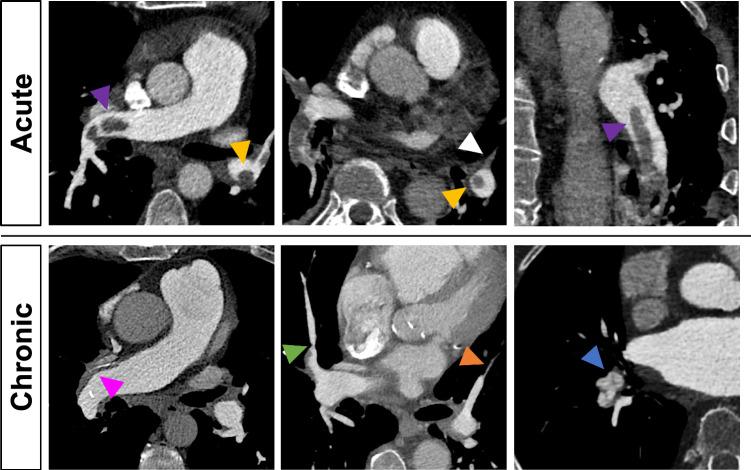

To evaluate dual-layer dual-energy computed tomography (dlDECT)-based characterization of thrombus composition for differentiation of acute pulmonary embolism (PE) and chronic thromboembolic pulmonary hypertension (CTEPH). This retrospective single center cohort study included 49 patients with acute PE and 33 patients with CTEPH who underwent CT pulmonary angiography on a dlDECT from 06/2016 to 06/2022. Conventional images), material specific images (virtual non-contrast [VNC], iodine density overlay [IDO], electron density [ED]), and virtual monoenergetic images (VMI) were analyzed. Regions-of-interest (ROIs) were manually placed in pulmonary artery thrombi, and morphological imaging characteristics for acute and chronic PE were assessed. Area under the receiver operating characteristics curve (AUC) of ROI measurements, morphological imaging features, and their combination in distinguishing between acute PE and CTEPH were evaluated. Compared to PE, thrombi in patients with CTEPH had lower attenuation on conventional images (Median [inter-quartile range]: 40 [35-47] HU vs 64 [52-83] HU) and VMI reconstructions (59 [46-72] HU vs 101 [80-123] HU) as well as decreased iodine uptake (IDO: 0.5 [0.2-1.0] vs 1.2 [0.5-1.8]; p for all < 0.001). Conventional images and VMI reconstructions were the most accurate for differentiating between acute and chronic thrombi (conventional: AUC 0.92, 95% CI 0.86-0.98; VMI: AUC 0.91, 95% CI 0.85-0.97). Main pulmonary artery (MPA) diameter combined with thrombus attenuation significantly increased the AUC compared to MPA diameter alone (p = 0.002 respectively). Thrombi in patients with CTEPH exhibit lower attenuation and reduced contrast enhancement. Analyzing attenuation in pulmonary thrombi may add diagnostic information to established morphological parameters in differentiating acute PE from CTEPH.

评估基于双层双能量计算机断层扫描(dlDECT)的血栓成分特征,以区分急性肺栓塞(PE)和慢性血栓栓塞性肺动脉高压(CTEPH)。这项回顾性单中心队列研究纳入了49例急性PE患者和33例CTEPH患者,这些患者在2016年6月至2022年6月期间接受了dlDECT的CT肺动脉造影检查。分析了常规图像、物质特异性图像(虚拟平扫[VNC]、碘密度叠加[IDO]、电子密度[ED])和虚拟单能量图像(VMI)。在肺动脉血栓中手动放置感兴趣区(ROIs),并评估急性和慢性PE的形态学成像特征。评估ROI测量的受试者操作特征曲线下面积(AUC)、形态学成像特征及其在区分急性PE和CTEPH中的组合。与PE相比,CTEPH患者的血栓在常规图像上的衰减较低(中位数[四分位间距]:40[35-47]HU对64[52-83]HU),在VMI重建上也较低(59[46-72]HU对101[80-123]HU),碘摄取减少(IDO:[0.2-1.0]对1.2[0.5-1.8];所有p<0.001)。常规图像和VMI重建在区分急性和慢性血栓方面最准确(常规:AUC 0.9, 95% CI 0.86-0.98;VMI:AUC 0.91, 95% CI 0.85-0.97)。与单独的主肺动脉(MPA)直径相比,MPA直径与血栓衰减相结合显著提高了AUC(分别为p = 0.002)。CTEPH患者的血栓表现出较低的衰减和对比增强减弱。分析肺血栓的衰减可能会为区分急性PE和CTEPH的既定形态学参数增加诊断信息。